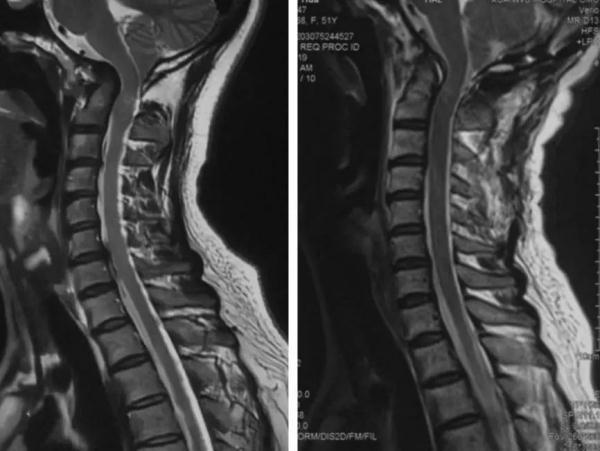

问诊、体格检查和辅助检查,缺一不可。临床经验丰富的按摩医生对病人实施任何手法治疗前,根据疾病的轻重缓急,一定需要有详细的颈椎病相关影像学检查资料(如颈椎的X线和核磁共振检查)。

颈椎的X线片

颈椎的核磁共振片